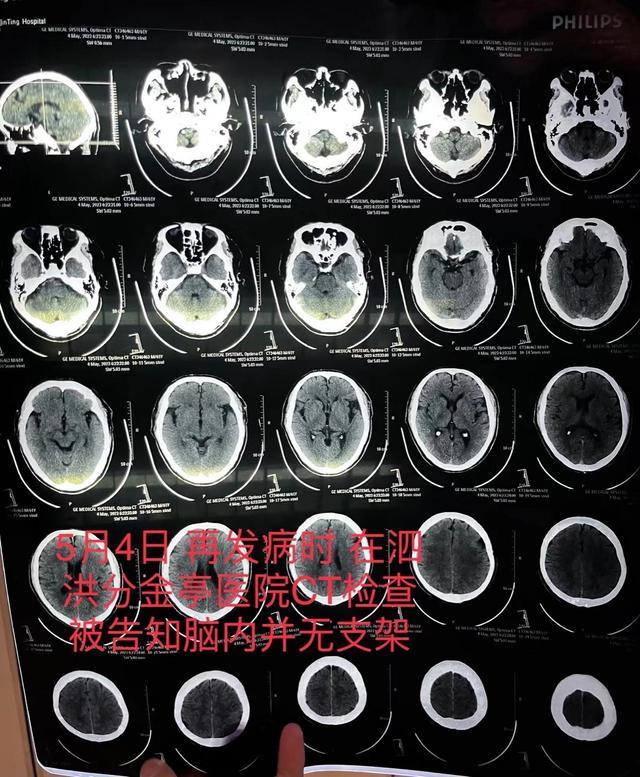

5月4日,朱先生的父亲突发严重脑梗,于是被送到了宿迁市泗洪县分金亭医院抢救。然而,医院在经过检查之后告知,朱先生的父亲颅内动脉严重堵塞,并且缺少支架。而这也让朱先生及其家属感到异常的震惊,在一个月前,他的父亲不是已经做过手术植入支架了吗?